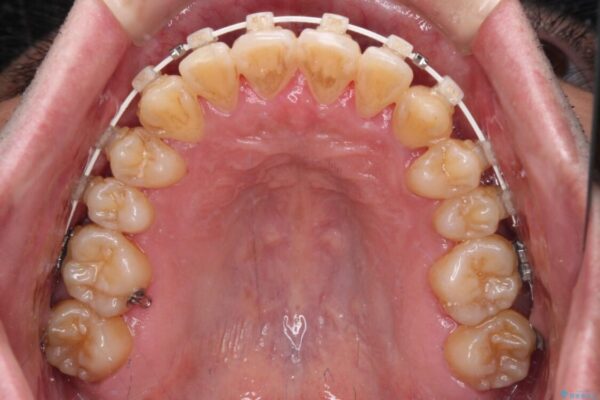

治療途中

• 八重歯とクロスバイト 目立たないワイヤー装置で矯正治療 治療途中画像